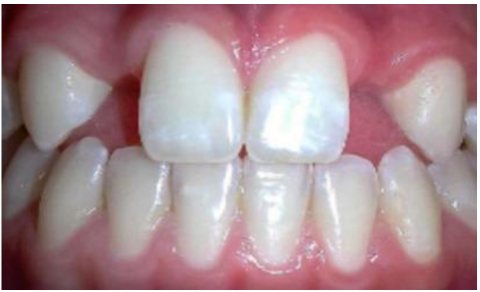

The dataset used in this study consists of 10,573 clinically sourced dental images, including contributions from publicly available repositories such as Kaggle. It provides a comprehensive foundation for training, validating, and testing the dental disease detection system [15]. The images are categorized into five distinct dental conditions: caries (2,382 images), gingivitis (2,349 images), hypodontia (1,251 images), mouth ulcers (2,541 images), and tooth discoloration (2,050 images) (Figure 1).

a

b

c

d

e

Figure 1. Dataset samples. (a) Caries, (b) Gingivitis, (c) Hypodontia, (d) Mouth ulcers, (e) Tooth discoloration